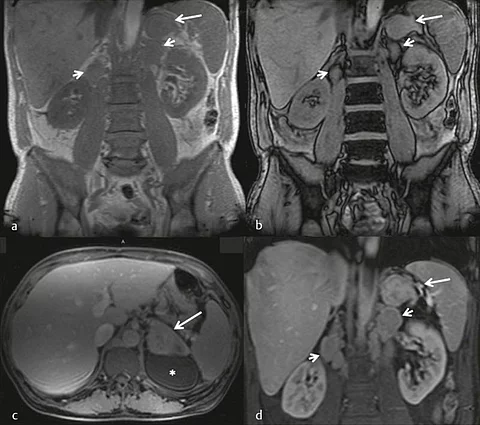

Im MRT zeigt sich ein 7×5×4cm großer solider Tumor der linken Nebenniere mit inhomogenen Signalintensitäten in den nativen T1- und T2- gewichteten Sequenzen. Innerhalb des Tumors zeigten sich eine Diffusionsrestriktion sowie zentrale Hypointensitäten in der kontrastmittelangehobenen T1-Wichtung mit randständiger Anreicherung (Bildergalerie).